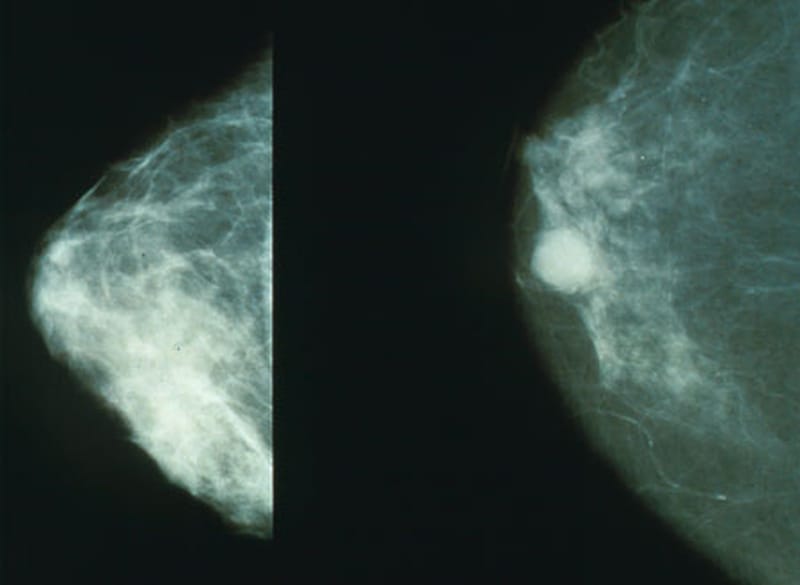

Thankfully, early detection can result in a better outcome. Mammograms for those above age 40 have led to a reduction of deaths by almost 20%. For younger women, ultrasound screening can be conducted, while women with a higher risk should consider it from the age of 30.